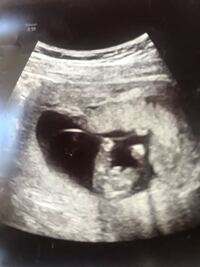

22週の男の子のエコー写真 22周めの男の子の写真です。足が上下にあり、真ん中にシンボルが見えますね。 23週目の男の子のエコー写真 右上がお尻、左下にむかって2本の足が、その間にシンボルがしっかりと見えています。 24 現在妊娠14週の妊婦です。 女の子希望なのですが、先日エコー で男の子のシンボルらしきものが写っており、とてもモヤモヤしております。 (矢印の部分)エコー 写真は、最初横を向いており、途中で顔をこちらに向けてくれたときのものです。 性別判断 女の子 エコー 突起 物 週 エコー 女の子 突起 物 リンクを取得;

14週での妊婦健診で男の子かもしれないけど へその緒かもしれないからまた来月だねと言われました。この 妊娠 13 エコー写真、性別わかりますか? 赤ちゃん 14 16週の4dエコーで性別 妊娠 15 16週の2D画像。男女の性別判断はできますか? 避妊 16 こんばんは!現在妻が妊娠18週な 女の子特有の線が見えたのに確定じゃないの(?_?) エコー写真を見るとうっすら長い何かが見えます。 これは臍の緒でしょうか? 立派な線が3本川の字なので私には女の子に見えるんですが 線が見えてて女の子から男の子に変わった方居ますか? 14週0日(14w0d・女の子)|62ki さん(24歳) エコー写真撮影時のエピソード: この子の前に一度授かった時は、同じ週数の時に前回の検診では確認できた心拍が確認出来ず流産をしていました。 今回も流産してしまったらと不安いっぱいの中、元気な姿を見せてくれて喜びでエコーを見ながら

出産 17週の女の子のエコーのふくらみ 17週になる2人目妊婦です。 性別は半々でわからないという結果でしたが、股間に山があり、男の子ではないかと思っています。 女の子を出産されたかた、17週目 質問No 男の子か女の子か気になる妊婦さん必見です! エコー検査での見え方の特徴もご紹介します。 性別がわかる時期っていつ?最初はみんな女の子だった。 実は、妊娠7週頃まで見た目はみんな「女の子」なんです。 この週数では、 男の子の場合、まだ精巣が ※エコー写真有♥ねんれい 22歳 妊娠週 23w3d 写真はお股を真下から撮ったものです。 性別は前回女の子と言われ、今回もやはり何も付いてないので女の子とのことでした^^体重が647gになっててこの1ヶ月間で3倍にまで成長していて驚きました! ! 身長は約30cmだそうです妊娠週0日 (w0d)の超音波